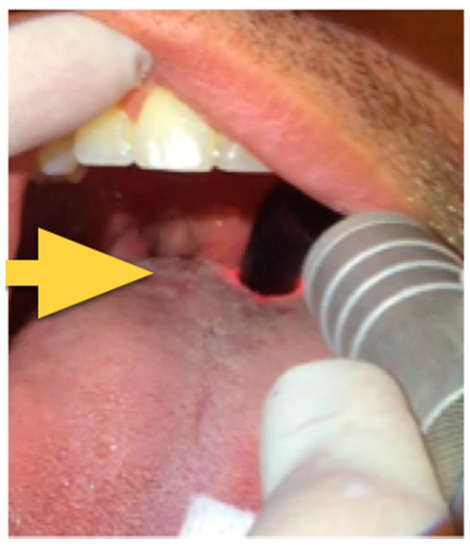

| 10 min of overlap on the so-called “main target point” using the straight glass rod. The main target point is the region of the soft palate midline posterior to the hard palate for an area of about 3 × 3 cm where the vibration of the soft palate begins (Figure 2) and, in the same region another three minutes of laser irradiation at 20 watts, frequency of 20,000 Hz, and 10 microseconds pulse duration (mean output of 4 watts) | |

| 10 min on lateral pharyngeal walls using either the straight or curved glass rod if needed (based on FNMM, which was compulsory before treatments in order to evaluate the exact region where the obstruction occurs) | |

| 15 min on the base of the tongue midline as far as possible holding the tongue with gauze (using the curved glass rod) if the FNMM showed an obstruction at that site. | |